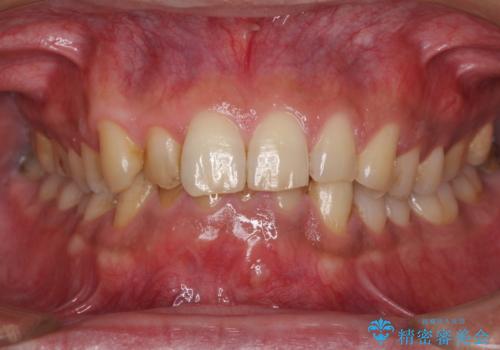

- 下の前歯がすり減って、痛みがあるとのことで来院された患者様です。

咬合力が強く、4本のうち3本の歯が失活しており、腫れや痛みが認められました。

3歯に根管治療を行い、その後4歯をオールセラミッククラウンにて補綴することとしました。